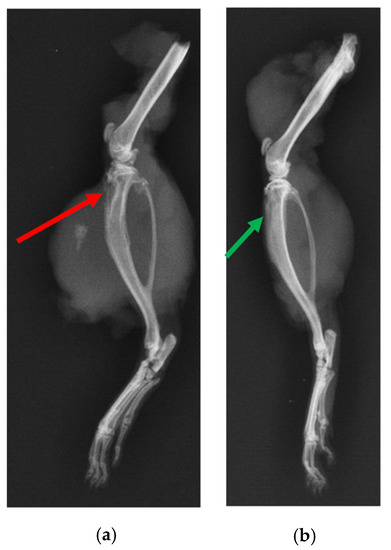

2.6.1. X-ray and μ-CT of Rat Bones

4.7.2. X-ray and μ-CT of Rat Bones